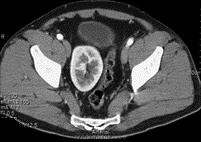

男,27岁,请根据所示图像,选择最可能诊断 ( )A、肾下垂B、游走肾C、腰段肾D、胸内肾E、盆腔肾

问题 男,27岁,请根据所示图像,选择最可能诊断 ( )

选项 A、肾下垂 B、游走肾 C、腰段肾 D、胸内肾 E、盆腔肾

答案 E